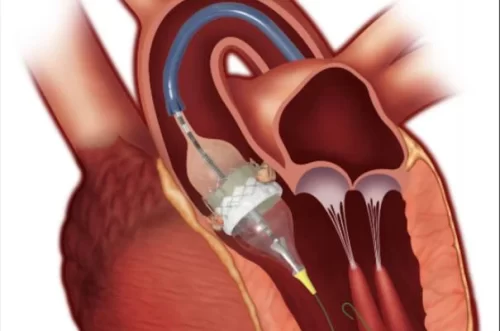

- عمل پیشرفته و موفقیتآمیز تاوی (TAVI)در ایران، در شهر مقدس مشهد توسط دکتر سید محسن جهرمی مقدم

- تنگی دریچه آئورت

- جراحی دریچه قلب